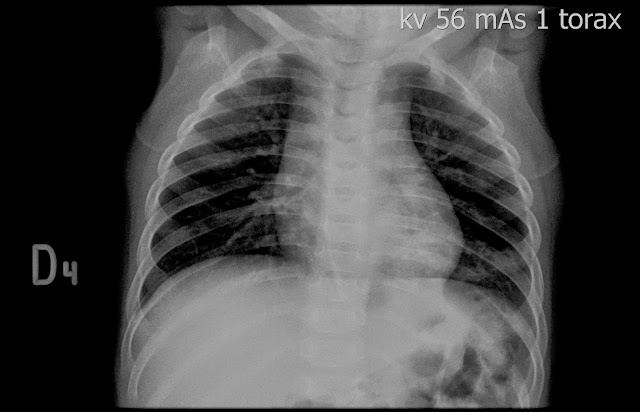

Caso interesante #2

¿A QUE CORRESPONDE Y PORQUE SE PRODUCE ESTA IMAGEN

IMÁGENES RADIOLÚCIDAS BILATERALES EN FORMA DE LUNA MENGUANTE ADYACENTE A LAS CABEZAS HUMERALES??????